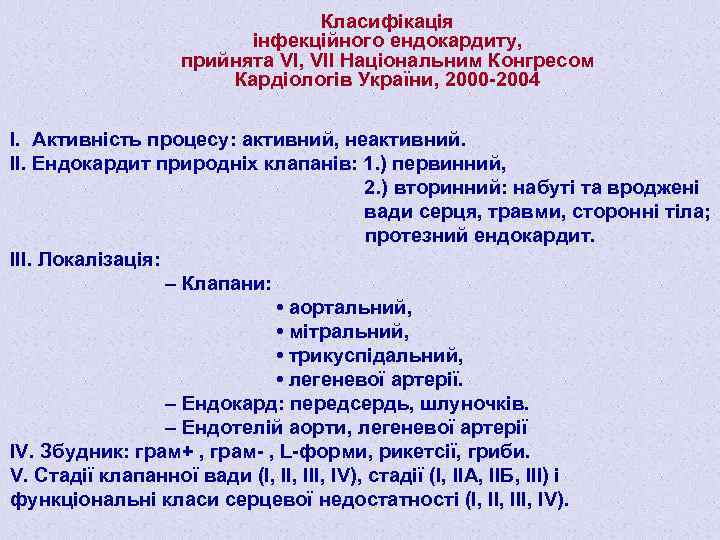

Класифікація інфекційного ендокардиту, прийнята VI, VІІ Національним Конгресом Кардіологів України, 2000 -2004 І. Активність процесу: активний, неактивний. ІІ. Ендокардит природніх клапанів: 1. ) первинний, 2. ) вторинний: набуті та вроджені вади серця, травми, сторонні тіла; протезний ендокардит. ІІІ. Локалізація: – Клапани: • аортальний, • мітральний, • трикуспідальний, • легеневої артерії. – Ендокард: передсердь, шлуночків. – Ендотелій аорти, легеневої артерії ІV. Збудник: грам+ , грам- , L-форми, рикетсії, гриби. V. Стадії клапанної вади (І, ІІІ, IV), стадії (І, ІІА, ІІБ, ІІІ) і функціональні класи серцевої недостатності (І, ІІІ, IV).